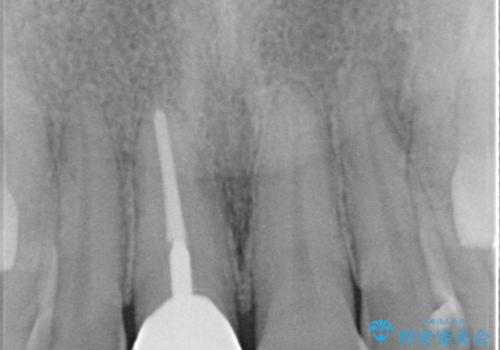

- 保険診療で装着した前歯のクラウンが変色して気になってきたとのことで来院された患者様です。

歯肉退縮による歯肉ラインの黒い縁も気になってきたとのことで、オールセラミッククラウンにて補綴治療を行うこととしました。